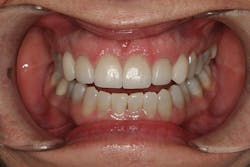

A 32-year-old white female presented for a cosmetic consultation. The patient reported that during her teenage years she had received orthodontic treatment to move her permanent maxillary canines mesially into the spaces that should have been occupied by her congenitally missing lateral incisors. She stated that her dentist, orthodontist, and oral surgeon had decided to place endosseous implants in the canine spaces due to the greater availability of bone in comparison to the bone available in the lateral positions (figure 1). As she grew older, she had become increasingly dissatisfied with the appearance of her smile and was seeking a more updated and esthetic solution (figure 2).

Figure 1

Figure 2